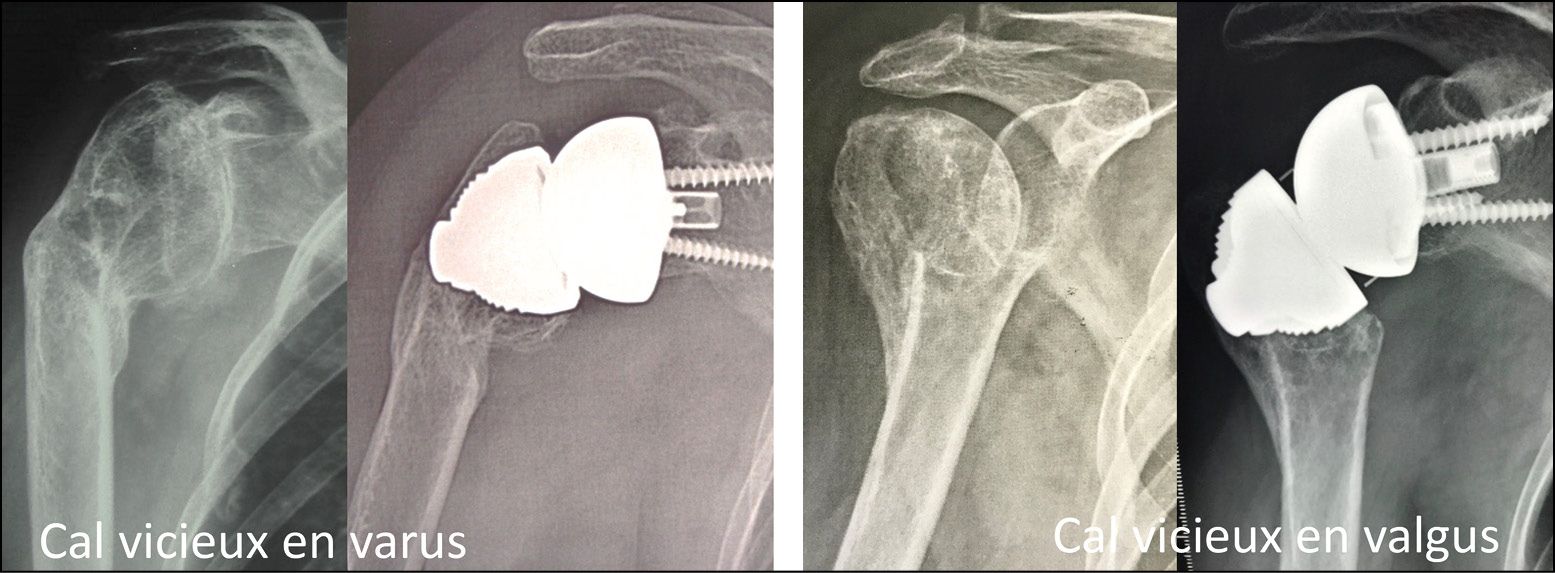

Malunion of the proximal humerus, if recent enough to have not affected the glenoid cartilage, is again a good indication: a stemless humeral implant makes it possible to restore the humeral head without any of the constraints caused by offsets or tuberosity transfer (Fig. 11).[4] Ballas R, Teissier P, Teissier J. Stemless shoulder prosthesis for treatment of proximal humeral malunion does not require tuberosity osteotomy. Int Orthop. 2016; 40:1473-9. doi: 10.1007/s00264-016-3138-y.

Osteoarthritis with rotator cuff tear in a young subject is a good indication for a reverse replacement because the absence of a stem makes the procedure less invasive (Fig. 14). Complex malunion can also be treated with a stemless reverse TSA, since the procedure removes the need for any diaphyseal or tuberosity transfer thus avoiding any corrective osteotomy which is rarely beneficial (Fig. 15).